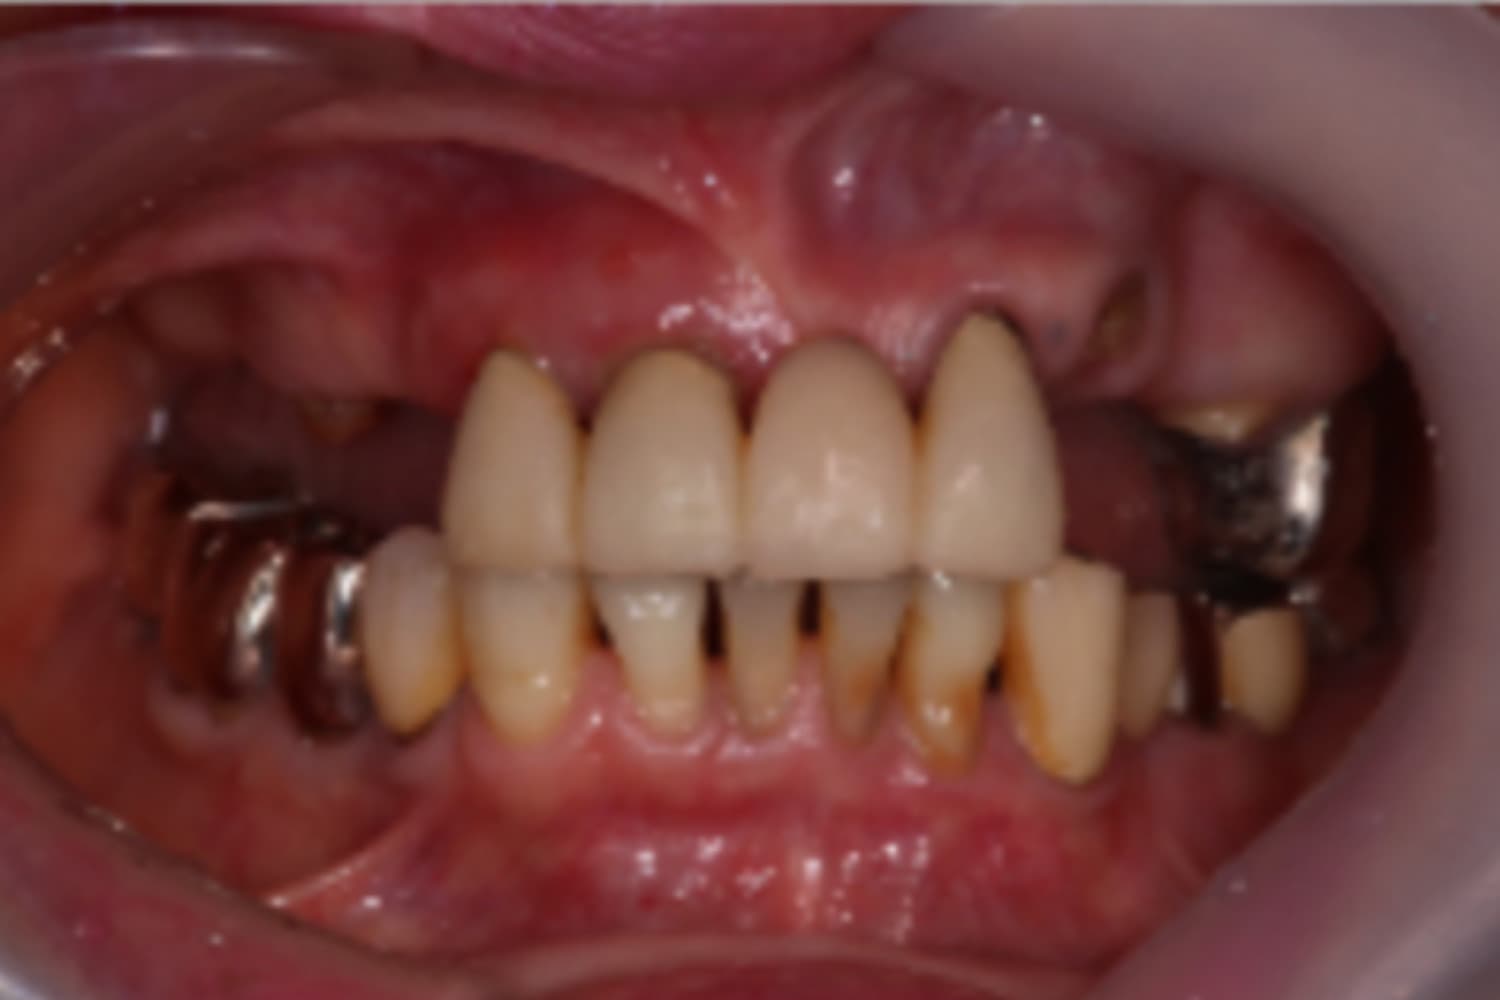

前歯のインプラント治療

Before

After

前歯4本を抜歯し、その後2本のインプラントと骨造成を行いました。上部構造は4本分です。

主訴

前歯が気になる

治療期間

12カ月

治療回数

12回

費用

1,276,000円

副作用・リスク

・重度歯周病により、感染リスクが高い ・インプラントとの結合不良が起きる可能性がある ・手術前に歯周病の十分なコントロールが必要 ・治療後も1〜2カ月ごとの定期メインテナンスが必須